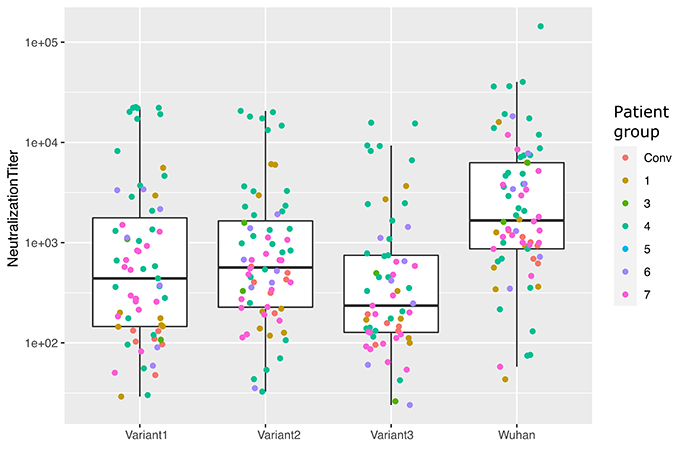

Comprender los efectos sobre la biología viral y las respuestas inmunitarias de las mutaciones en la espícula viral del SARS-CoV-2

El SARS-CoV-2 demostró una notable capacidad de adaptación, y se observaron numerosas variantes arrasando la población. Comprender el efecto biológico sobre la biología viral y el escape inmunológico de estas mutaciones es esencial para emplear medidas sanitarias adecuadas. Para poder valorar el rol de la mutación de la espícula viral del SARS-CoV-2, combinamos sistemas réplica-competentes y réplica-incompetentes que nos permiten determinar la inefectividad, estabilidad y evasión inmunológica de varias mutaciones espiculares. Este trabajo se lleva a cabo en colaboración con numerosos grupos de investigación y personales hospitalarios para poder evaluar nuevas mutaciones en tiempo real.